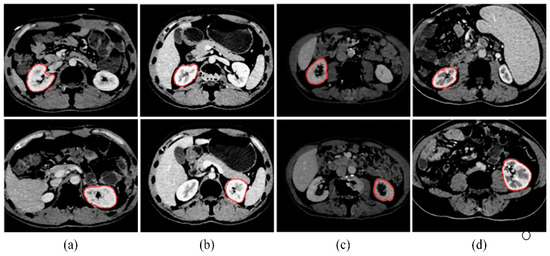

Kidney segmentation from abdominal computed tomography (CT) images is essential for computer-aided kidney diagnosis, pathology detection, and surgical planning. This paper introduces a kidney segmentation method for clinical contrast-enhanced CT images. First, it begins with shape-based preprocessing to remove the spine and ribs. [...] Read more.

Kidney segmentation from abdominal computed tomography (CT) images is essential for computer-aided kidney diagnosis, pathology detection, and surgical planning. This paper introduces a kidney segmentation method for clinical contrast-enhanced CT images. First, it begins with shape-based preprocessing to remove the spine and ribs. Second, a novel clustering algorithm and an initial kidney selection strategy are utilized to locate the initial slices and contours. Finally, an adaptive narrow-band approach based on active contours is developed, followed by a clustering postprocessing to address issues with concave parts. Experimental results demonstrate the high segmentation performance of the proposed method, achieving a Dice Similarity Coefficient of 97.4 ± 1.0% and an Average Symmetric Surface Distance of 0.5 ± 0.2 mm across twenty sequences. Notably, this method eliminates the need for manually setting initial contours and can handle intensity inhomogeneity and varying kidney shapes without extensive training or statistical modeling. Full article